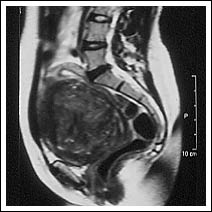

Scans - Patient 3

| At 26th January 1998 - large 12cm full thickness fibroid. |

At 21st July

1998 - post embolisation showing 90% shrinkage of

fibroid. |

| Sagittal Magnetic Resonance Imaging scans showing fibroid before and after treatment. | |||